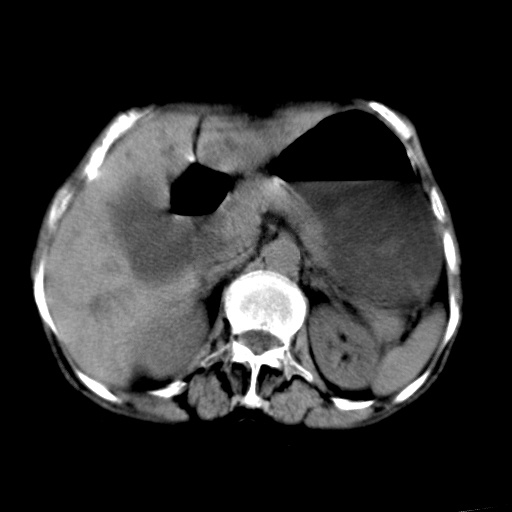

以下是引用杀毒软件在2009-3-4 17:38:00的发言:[br]为何没有喝照影剂呀? 胆总管及肝内胆管扩张,增强吧。[br][br]考虑-----十二指肠占位----建议----十二指肠镜检查[br][br]

以下是引用jiangjing在2009-3-4 17:45:00的发言:[br]低位胆道梗阻。十二指肠降段局部管壁增厚。扫描效果不理想,建议ct增强及ercp。

以下是引用杀毒软件在2009-3-4 17:38:00的发言:[br]为何没有喝照影剂呀? 胆总管及肝内胆管扩张,。增强吧。[br][br]考虑-----十二指肠占位----建议----十二指肠镜检查[br][br][br][br][本贴已被 杀毒软件 于 2009-3-4 17:56:38 修改过]